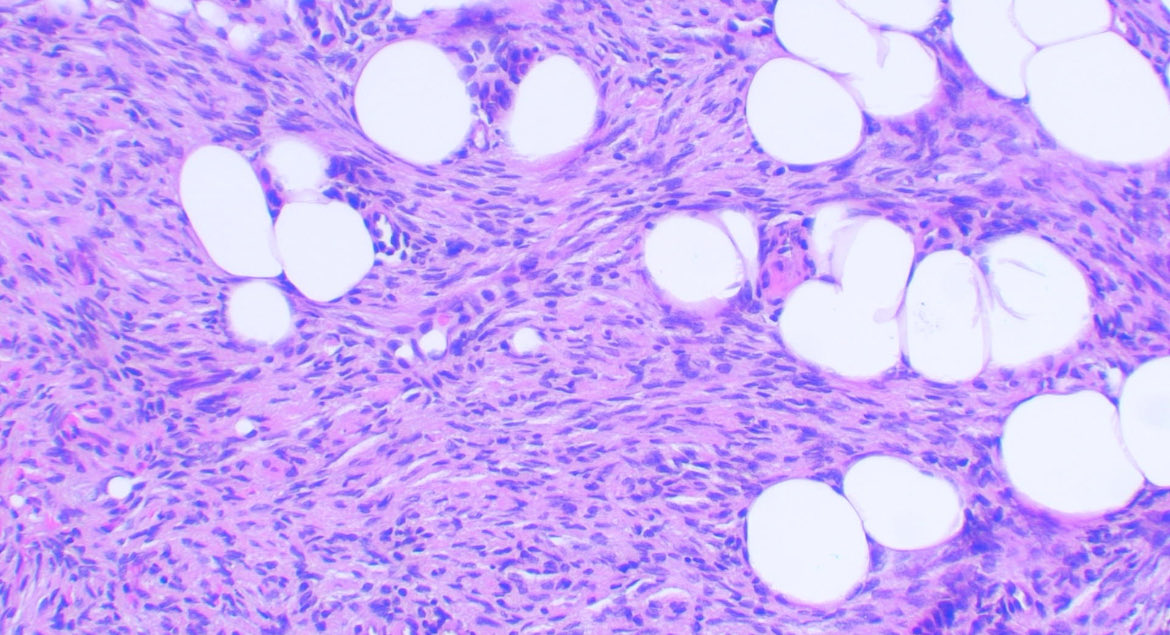

Male 75y/o Breast lesion Myofibroblastoma HE, CD34, Desmin,ER #breast #BreastCancerAwareness #path #pathology #Medicine